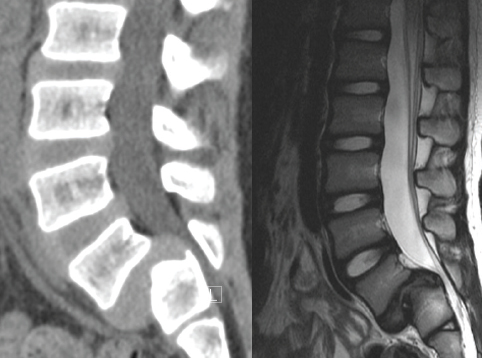

* Dowiedz się jakie badania radiologiczne są przydatne i jak z nich korzystać

Kręgozmyk wynika z niestabilności pourazowej lub czynnościowej kręgosłupa o zróżnicowanej etiologii. Poznanie sprzyjających warunków do przemieszczenia kręgów względem siebie w płaszczyźnie strzałkowej pozwoli na skuteczniejszą profilaktykę wtórną. a także - co jest celem terapii – zahamowanie postępu przemieszczenia. Określenie struktur, których napięcie lub niewydolność wpływa na ruchomość połączenia L5/S1, w przypadku nutacji i kontrnutacji kości krzyżowej, w zróżnicowanej budowie miednicy przyczyni się do realizacji powyższego celu.